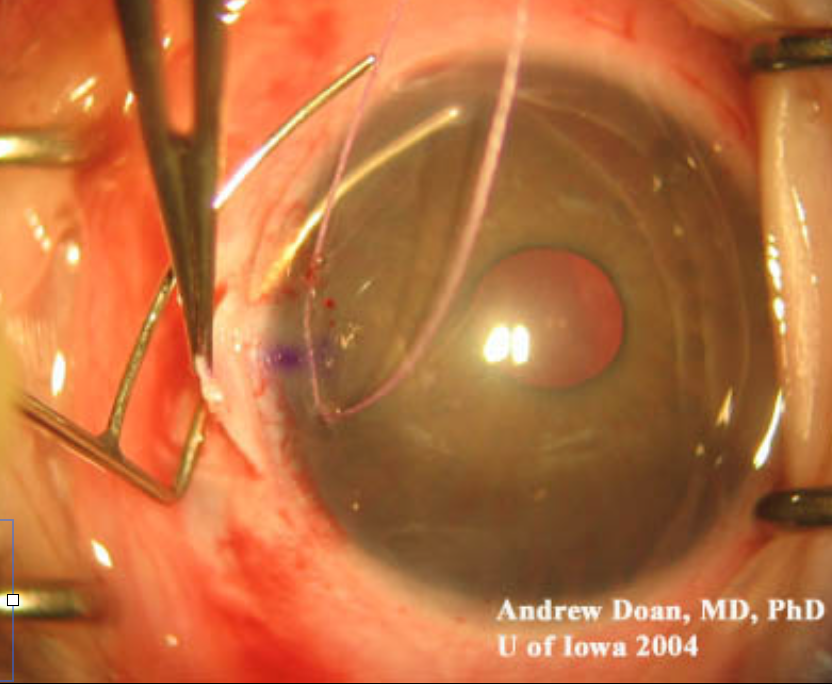

Mal-formação angular semelhante ao GCP - Tratamento com cirurgia angular (Trabeculotomia)

Glaucoma pós-trabecular (↑PVE) - Tratamento clínico/Trabeculectomia - Risco aumentado de efusão/hemorragia supracoroidal

Cirúrgico - Trabeculectomia + MMC

Evitar áreas de vasos dilatados e evitar bloqueios se anormalidades orbitárias

Realizar suturas apertadas e lise tardia - evitar hipotonia e hemorragia supracoroidal